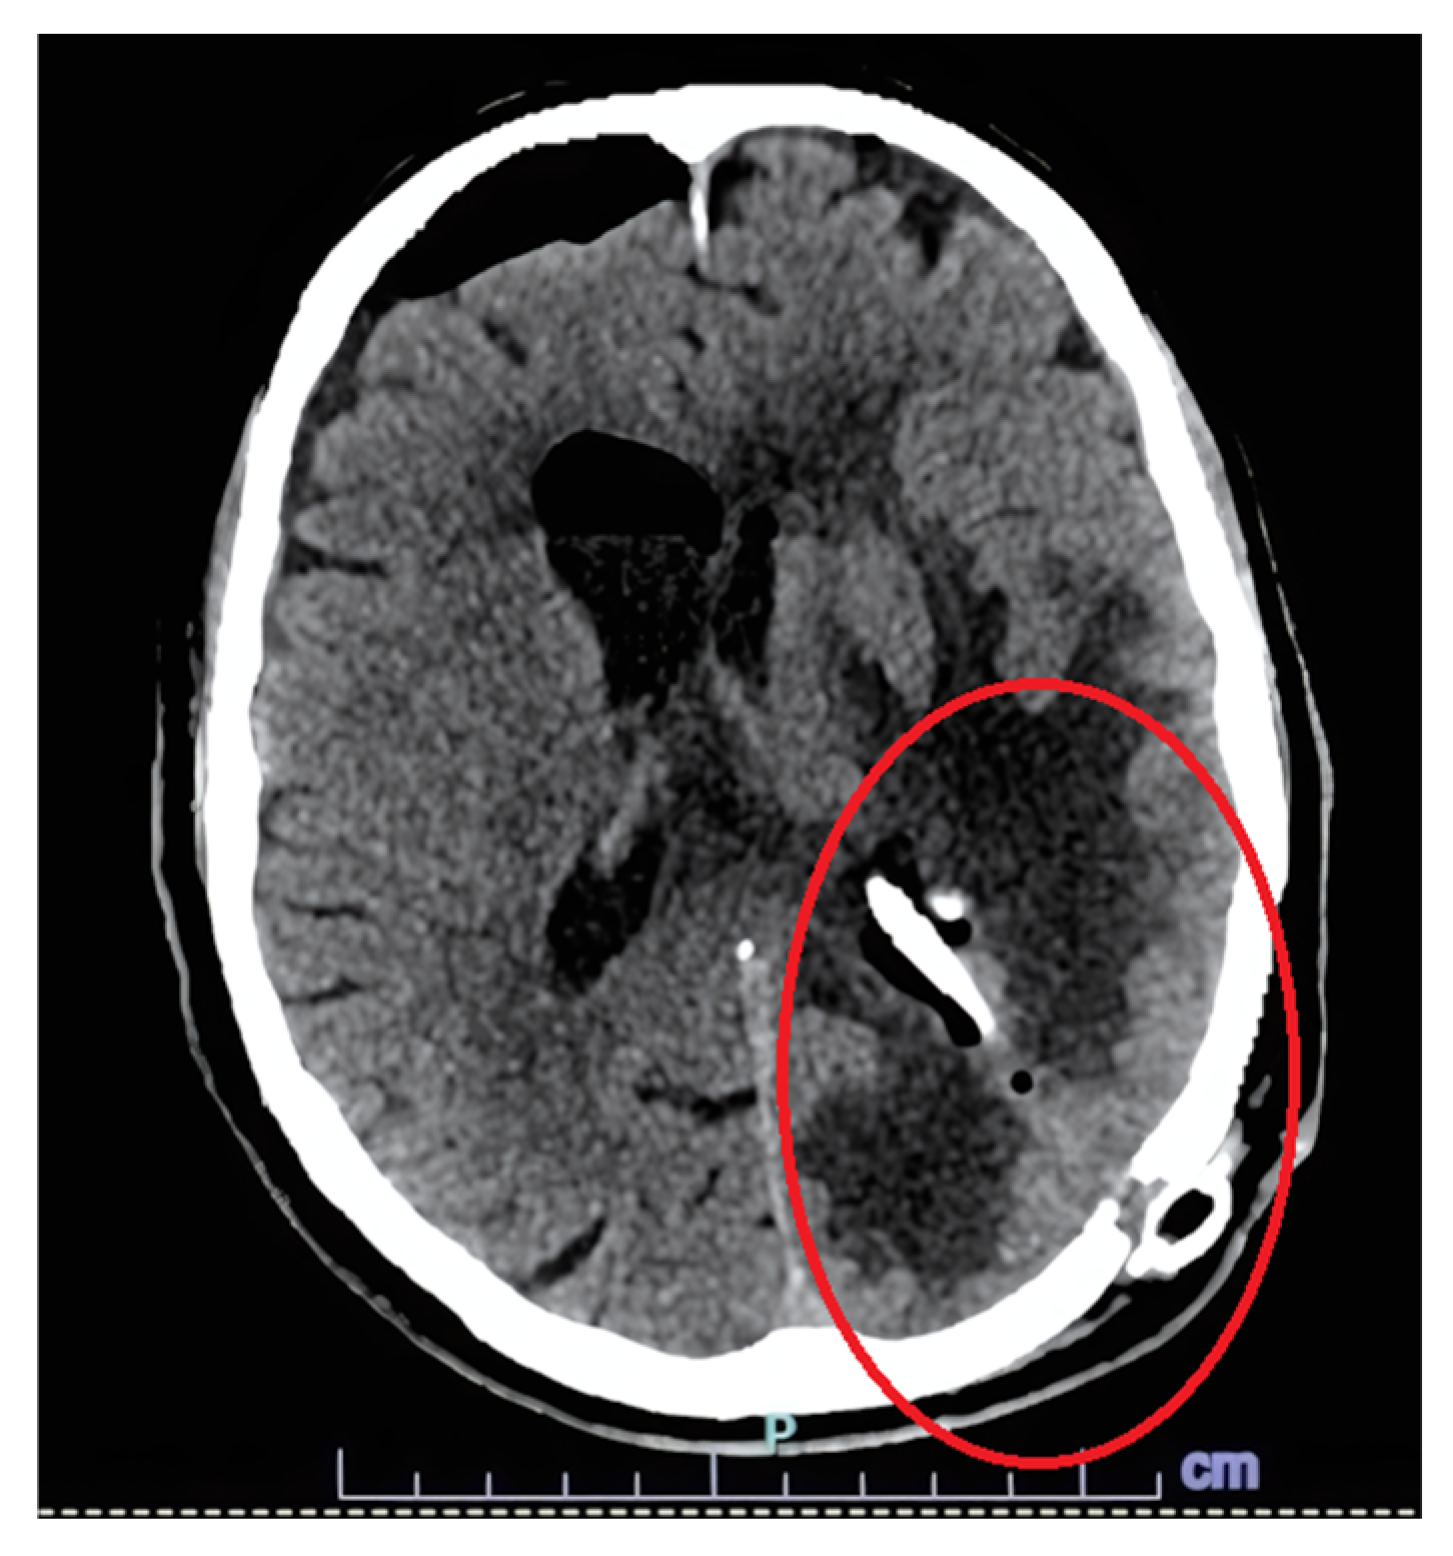

| 8 | Our case | 77/M | Fever, confusion | Right frontal lobe hyperintensity and left lateral ventricle exclusion. | Encephalitis and ventriculitis | CSF | Pleocytosis, hypoglycorrhachia, and hyperproteinorrachia | INH + RIF + EMB + LEV; LIN (2 weeks) | No | Yes | 14 | SR |